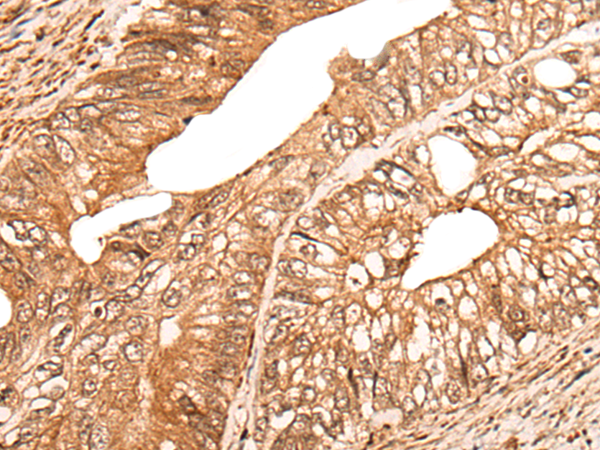

IHC positive control:

Human colorectal cancer